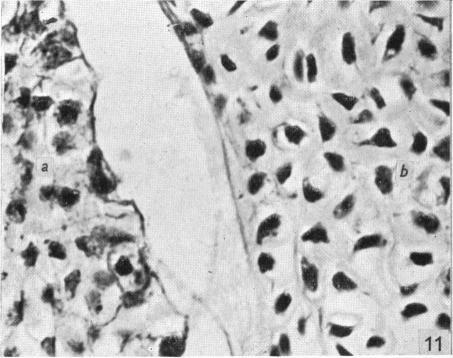

Observations on the prenatal development of the intervertebral disc in man.

J Anat. 1951 Jul;85(3):260-74.